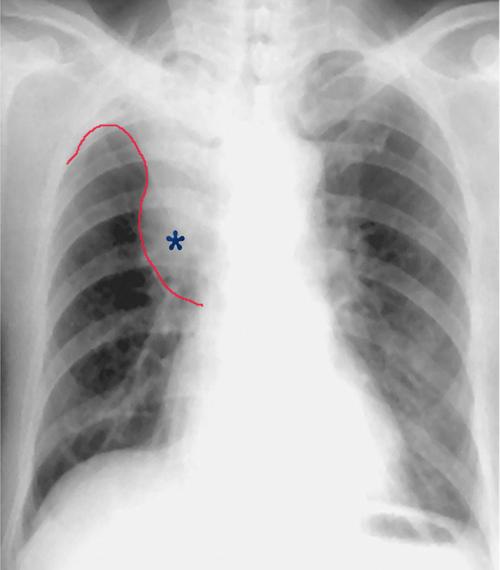

鳞状细胞癌伴支气管阻塞和肺不张

中央型肺癌的横s或者反s征,是指右侧中央型肺癌的正位x光胸片上的典型